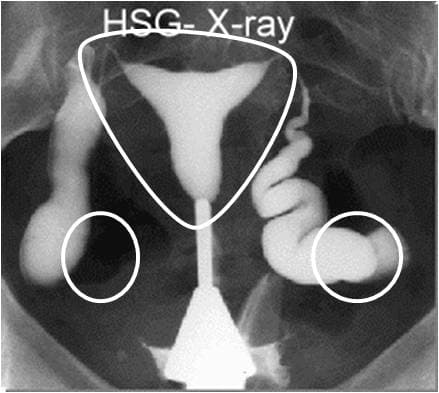

Vì vậy, để biết chính xác hiện tượng này, chị em cần tiến hành thăm khám, chụp X quang tử cung, vòi trứng, siêu âm nội soi buồng trứng… để xác định bệnh, chứ không nên chỉ dựa vào những biểu hiện lâm sàng bên ngoài.